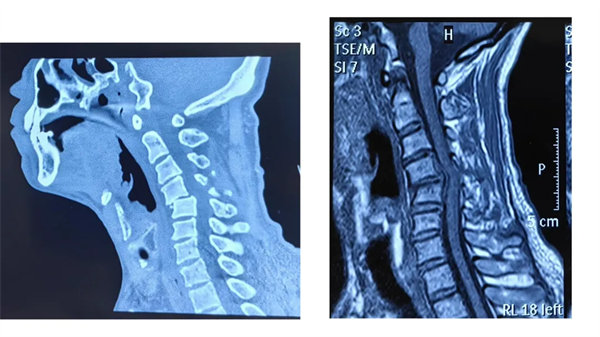

術(shù)前

患者受傷后曾在外院接受保守治療,但肢體麻木癥狀持續(xù)存在。轉(zhuǎn)入我院時,頸椎CT及MRI顯示:頸4/5椎骨折脫位,脊髓受壓明顯,若不手術(shù)治療,可能面臨永久性神經(jīng)功能障礙。我院骨四科團(tuán)隊(duì),制定了前路ACDF手術(shù)方案:通過頸前側(cè)入路,切開復(fù)位、切除椎間盤,解除脊髓壓迫,同時植入融合器、鈦板固定,重建頸椎正常序列及穩(wěn)定性。術(shù)后患者麻木感消失,復(fù)查顯示頸椎序列恢復(fù)良好,目前已康復(fù)出院。